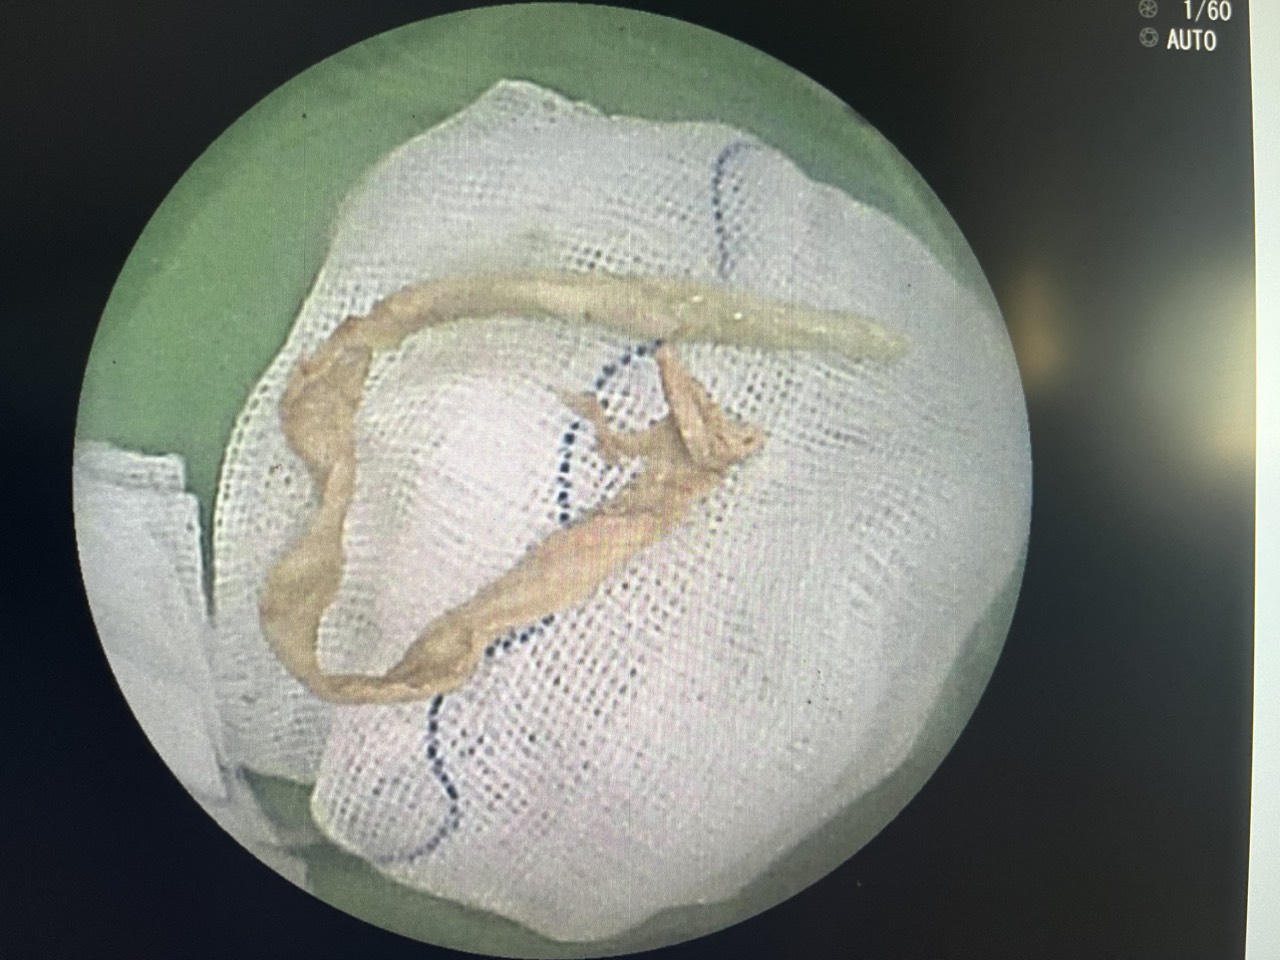

Dị vật được lấy ra sau nội soi phế quản |

Sau khi thay canyun thành công, ê-kíp tiếp tục thực hiện nội soi phế quản ống mềm có thực hiện tiền mê, ghi nhận lòng phế quản bên phải có dị vật là đoạn giấy dài chèn bít phần lớn lòng phế quản phải. Do dị vật là giấy, sau thời gian thấm dịch ở đường thở, giấy đã mềm, việc lấy ra rất khó khăn. Các bác sĩ cẩn thận phối hợp kẹp và dụng cụ hút để lấy dị vật. Sau gần 1 giờ nỗ lực, ê-kíp nội soi đã lấy thành công dị vật đoạn khăn giấy được se lại kích thước khoảng 0.5 x 15cm.